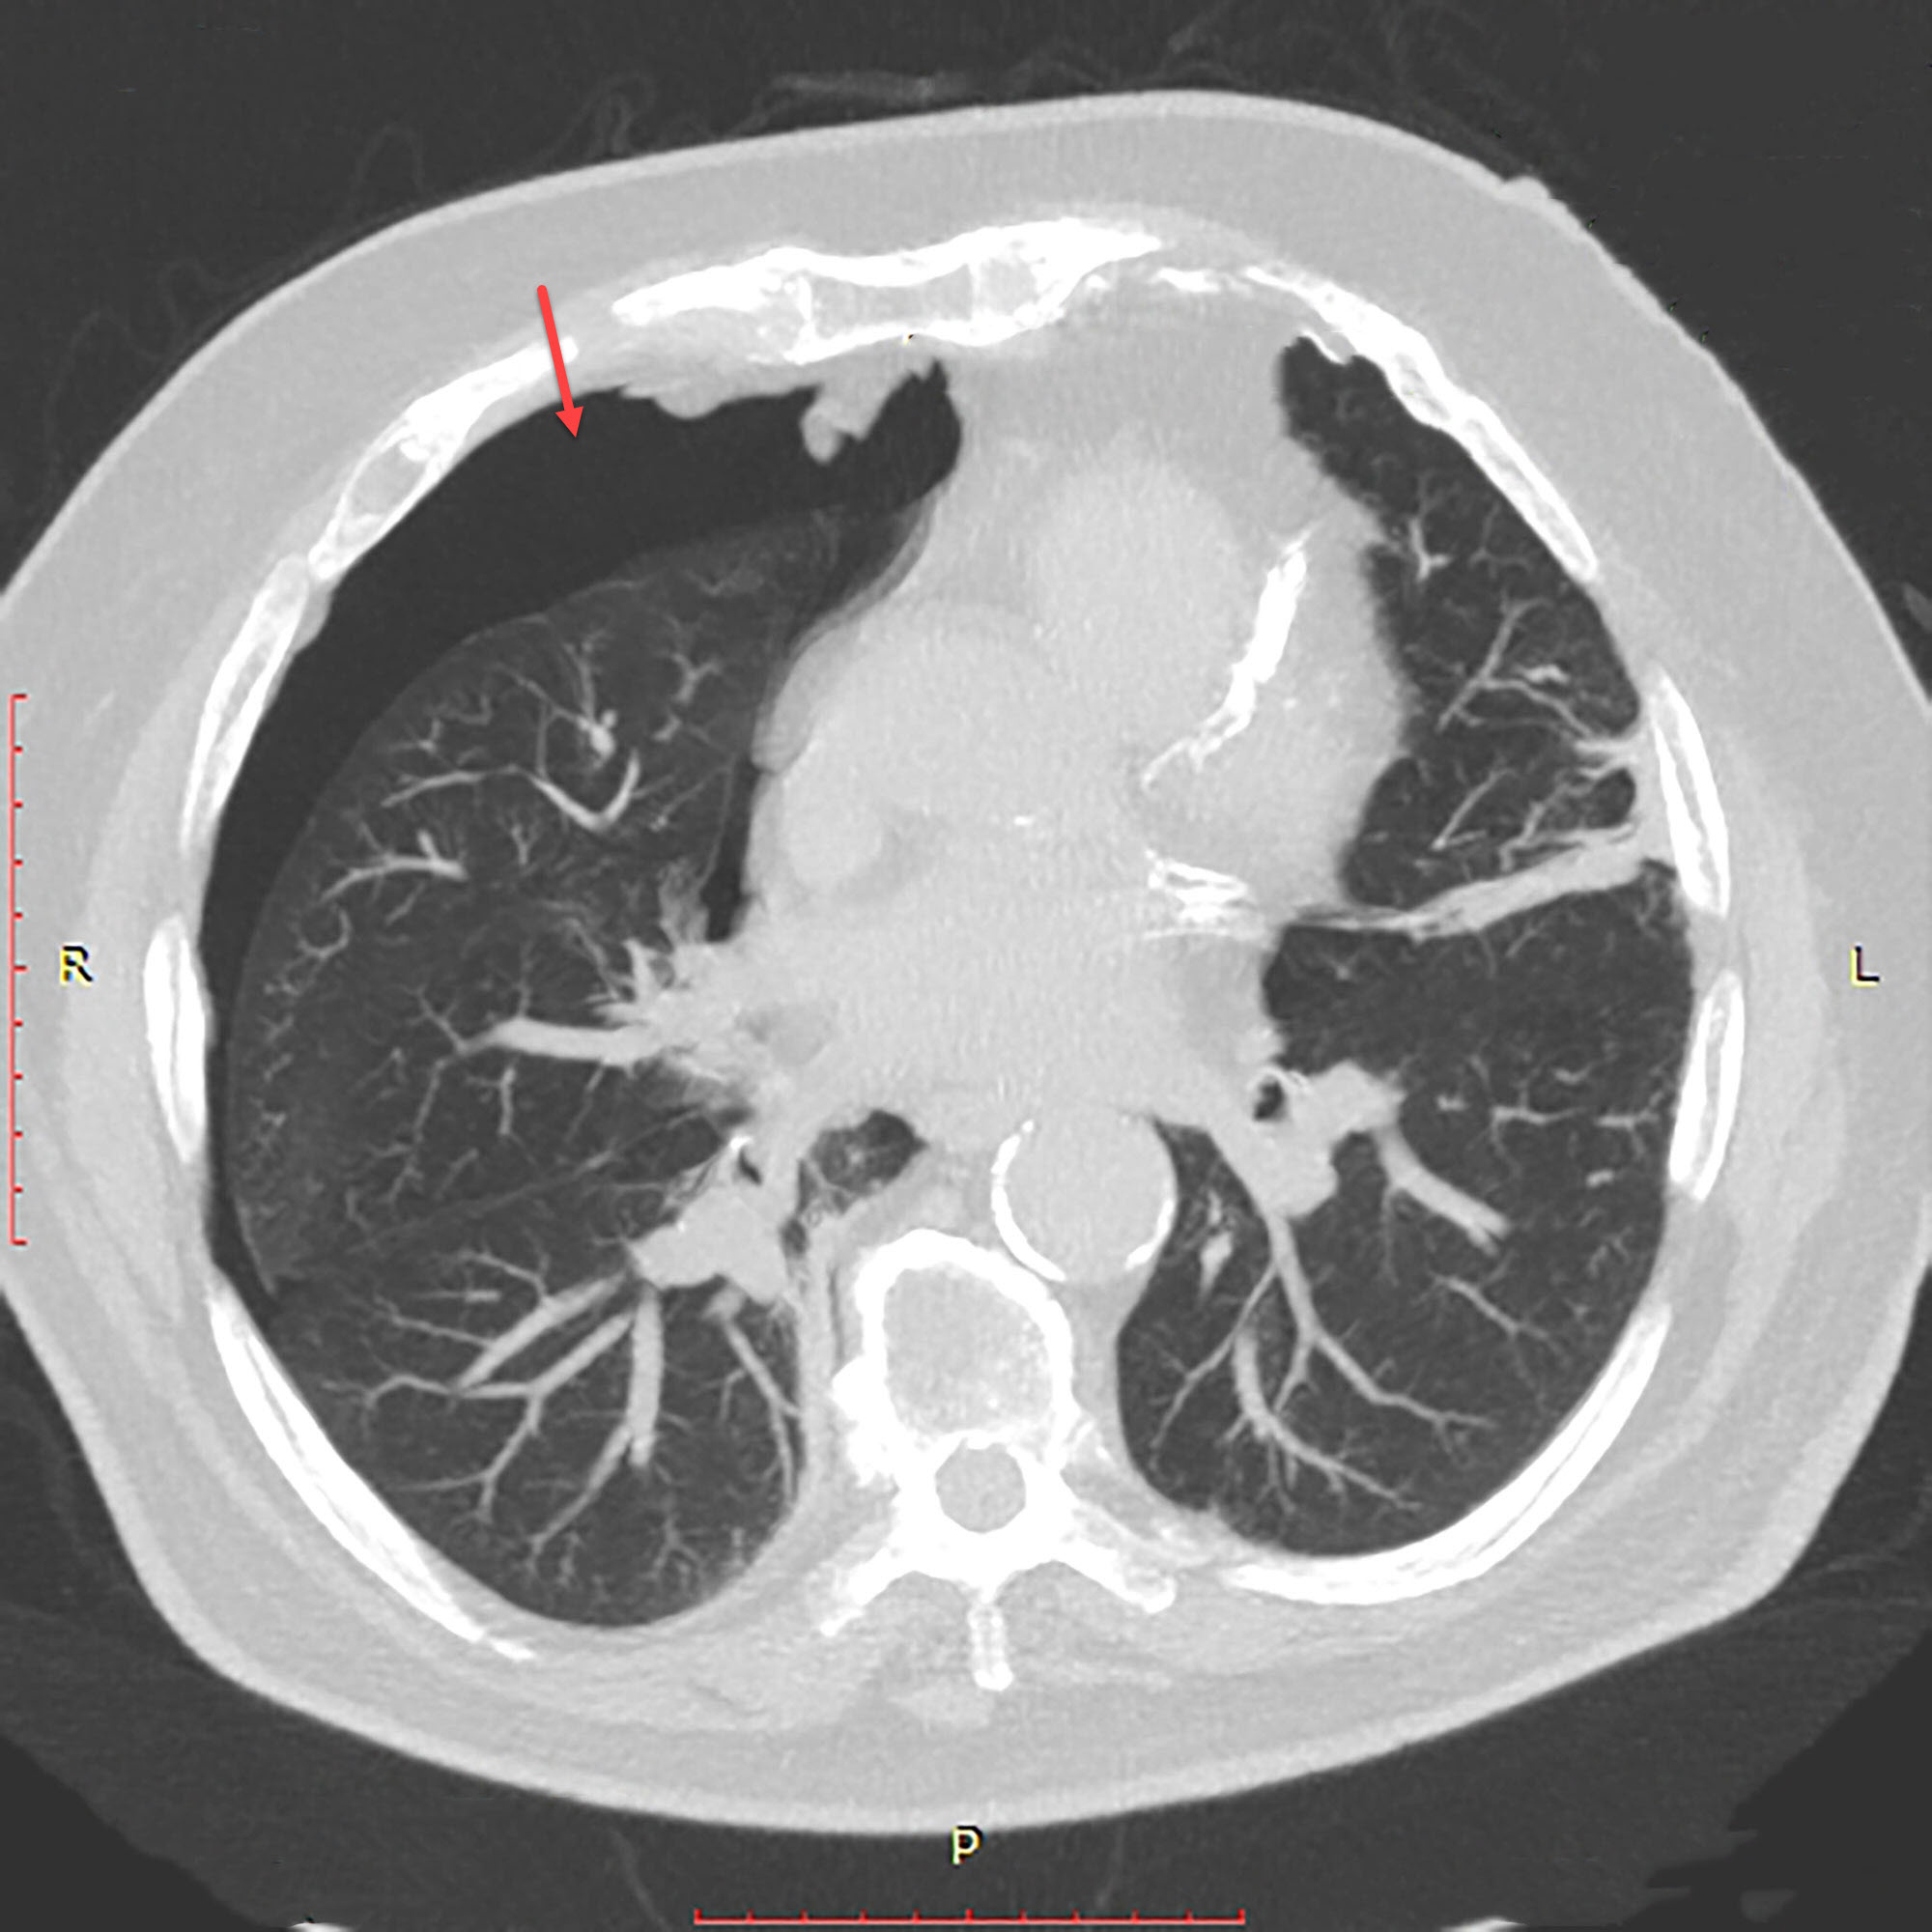

Chest Xray of left sided pneumothorax. Download Scientific Diagram